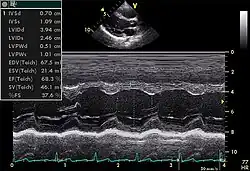

M-mode

Motion mode, though less commonly used, plays an important role in modern echocardiography. It has an advantage over 2D echocardiography due to its high temporal resolution (up to 1000 frames/sec). Examples of its use include accurate measurement of LV size, assessment for presence of cardiac tamponade, and assessment of RV function with TAPSE (tricuspid annular systolic plane excursion).